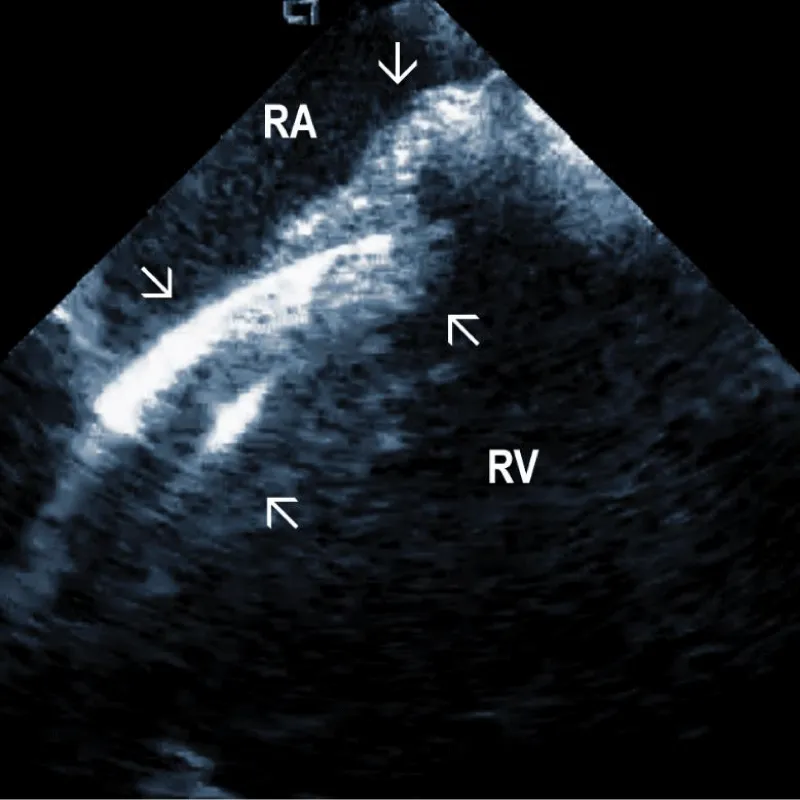

At the beginning of the procedure, ICE is introduced into the right ventricle to check and document possible pericardial effusion and left or right ventricular function. The course of the lead within the right ventricle is visible (Figure 1A). In addition, attachments of the right ventricular leads to cardiac structures could be seen, and the tip of the lead can be localized (Figure 1B).

Figure 1A: The course of two pacemaker leads (arrows) within the right ventricle (RV). The ICE catheter is positioned in the basal RV.

Figure 1B: ICD lead crossing the tricuspid valve between the right atrium (RA) and right ventricle (RV). Arrows mark lead adherent echodensities. The ICE catheter is positioned in the RA.